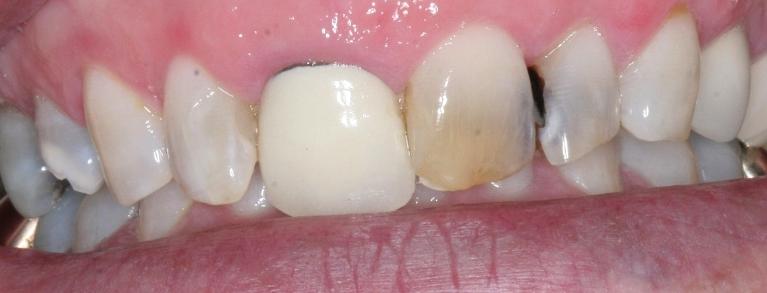

- Darkening or discoloration of the tooth

When you arrive at our office, Dr. Haag will perform a visual inspection and take x-rays to determine if the root canal is infected. If it is, a root canal treatment is in order.

Once we are satisfied that there is no longer any sign of infection, we fill the tooth using a special sealant. A crown is placed over the exterior of the tooth to restore the functioning of the tooth and prevent further damage.

Thanks to CEREC technology, the crown can be created right here in our office and placed on the same day, eliminating the need for a return trip to the dentist. In addition, your crown is customized to perfectly match your own teeth, so it looks and functions just like a normal tooth.